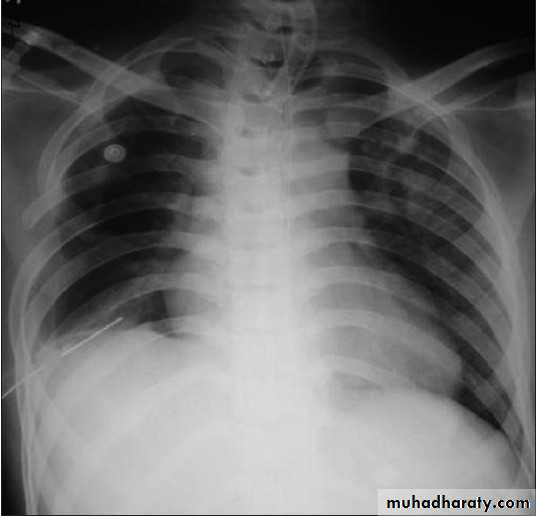

Patient with fever, rigor and dyspnea